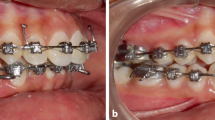

The current finite element analysis simulated a clinical situation where the mandible was positioned forward via a new fixed functional appliance design, EFA. The appliance could be easily constructed in the laboratory.

A two-dimensional model was prepared on ANSYS GUI, to simulate the lower part of the skull. The model dimensions were taken from literature (Panigrahi and Vineeth 2009). Two types of elements were used to build the model: Shell 3D 4node 181 with 6 degrees of freedom to mesh the bone and Link 180 as spar element to represent the appliance effect (Kohnke 2013). The applied force was 2 N propulsive force, as the forces generated by fixed functional appliances range from 150 to 200 g, i.e., 1.47 to 1.98 N (Karacay et al. 2006; Nalbantgil et al. 2005). The meshing process resulted in 59,386 nodes and 30,459 elements. As presented in Fig. 1, after the model meshing, the upper line, connecting the model to the skull, was set fixed in place as boundary condition.